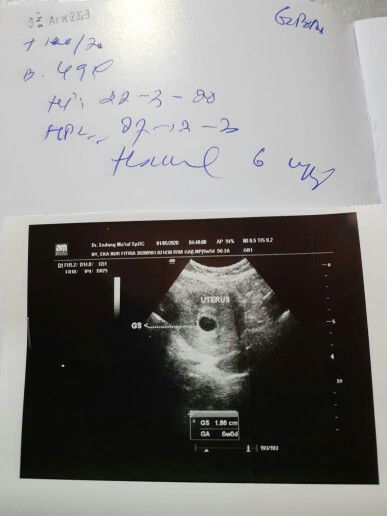

Bun saya hamil 6 week, tapi udh semingguan ini keluar flek coklat terus setiap hari, kemarin sudah cek ke dokter kata dokter nggkpapa dan cuma dikasi vitamin aja sama obat penguat kandungan, tapi sampai sekarang masih keluar flek coklat gtu, kira2 ada apa ya bun dengan kandungan saya? Mungkin bunda ada yg pernah mengalami hal yg sama spt saya